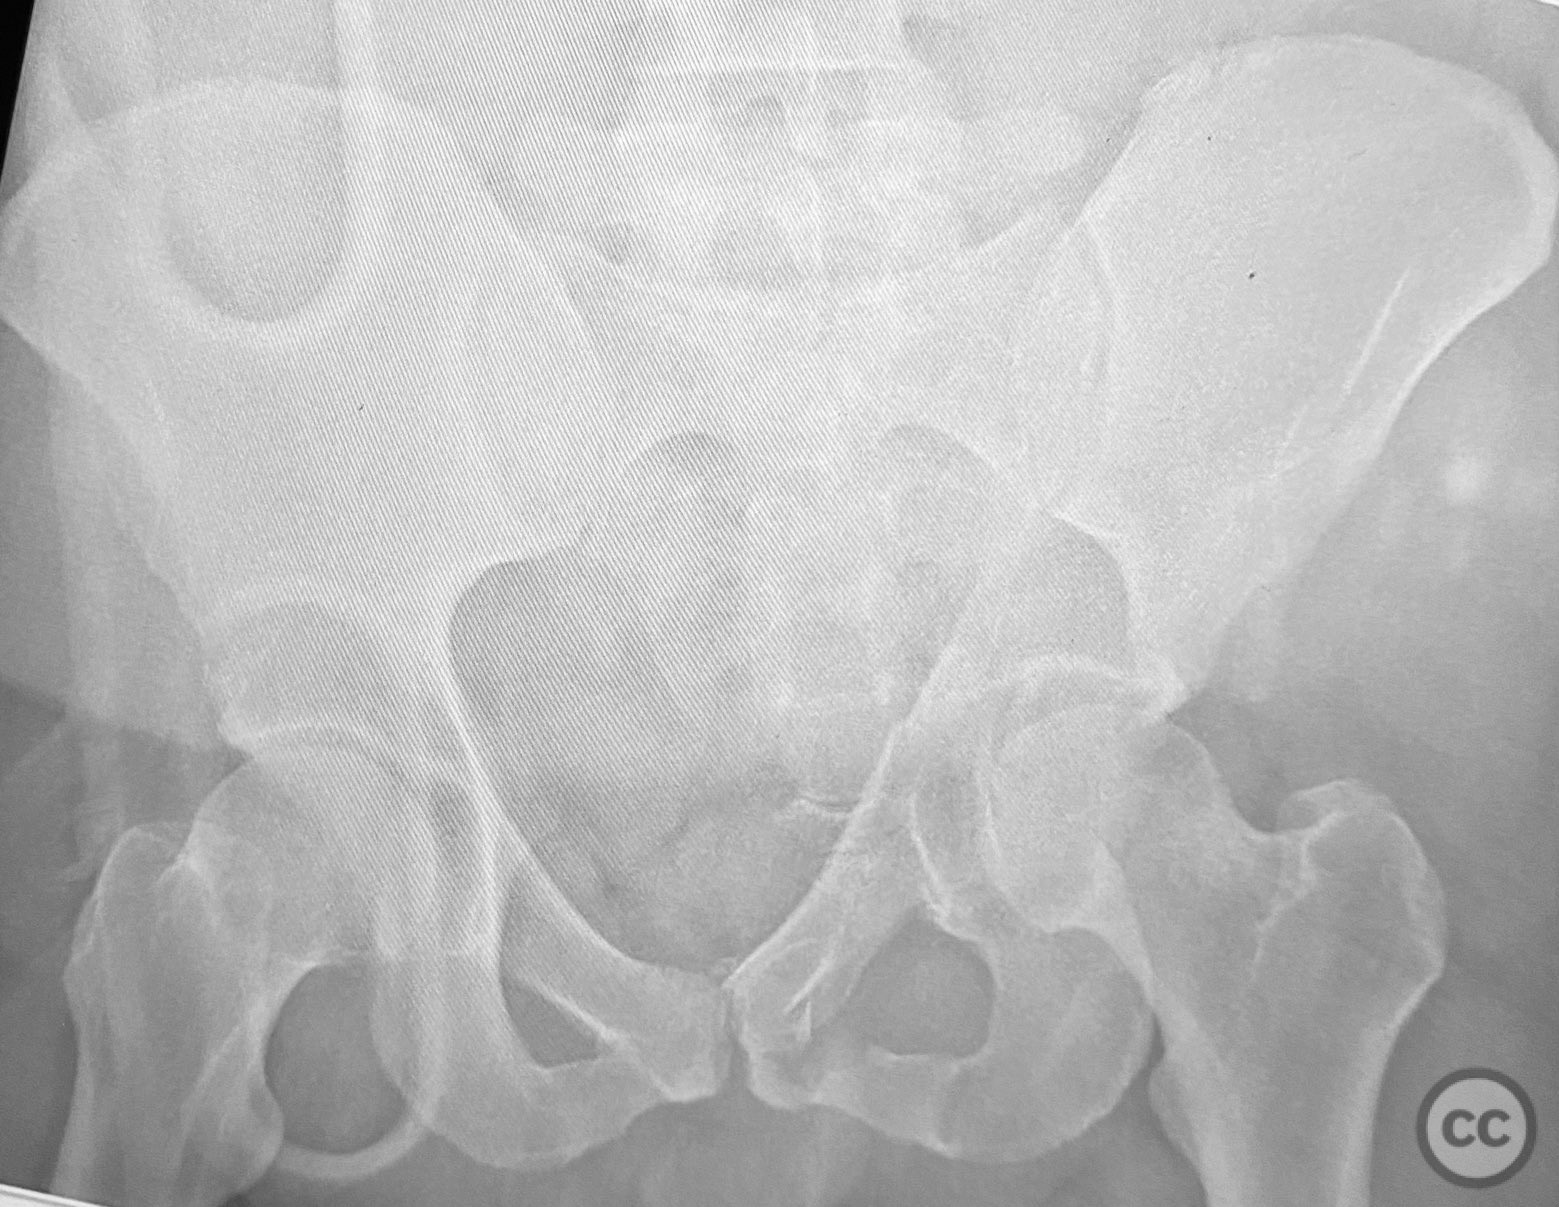

Clinical and radiological findings:  A patient presented with a displaced associated both column acetabular fracture, characterized radiographically by the presence of the "spur sign" on the anteroposterior (AP) pelvis film, indicating the caudal aspect of the intact ilium exposed by medial displacement of the articular fragments. The spur was more clearly visualized on the obturator oblique rendered image. Axial computed tomography (CT) images demonstrated the intact ilium, medially displaced anterior column (AC) and posterior column (PC) fragments, and provided detailed visualization of surrounding soft tissues, including vascular structures enhanced by contrast. Multiplanar CT reconstructions (axial, sagittal, coronal) and 3D renderings were utilized for comprehensive fracture and soft tissue assessment. The patient’s overall clinical condition was a significant factor in surgical planning.